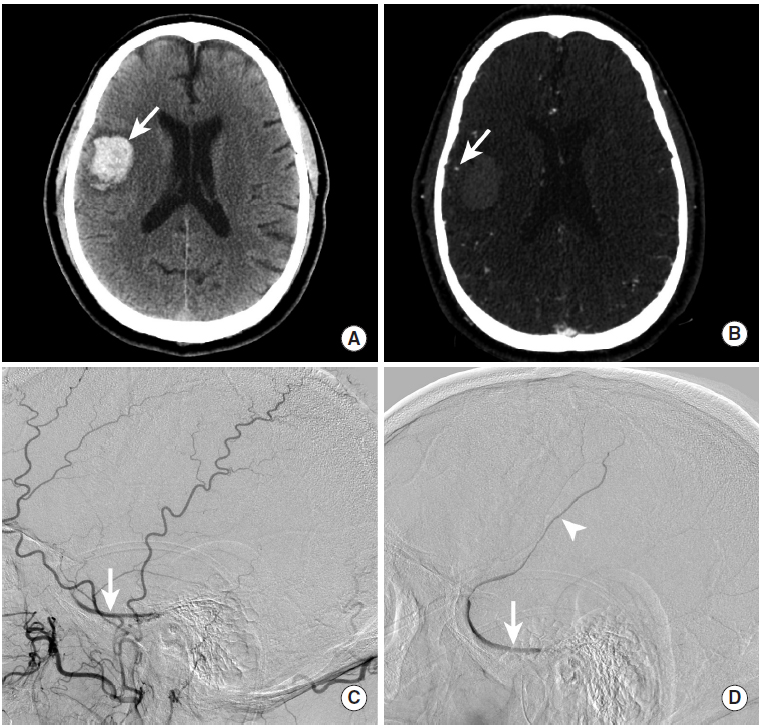

图14

本例为继发于硬脑膜动静脉瘘破裂的脑实质内出血。

图A:CT平扫显示右侧颞叶内高密度影,提示脑实质内出血(长尾箭头)。

图B:CTA显示出血区域边缘覆盖着皮层静脉(长尾箭头)。

图C:自右侧颈外动脉注射造影剂后,动脉期可见右蝶顶窦对比欠清晰(长尾箭头。

图D:DSA延迟期,右侧蝶顶窦(长尾箭头)和皮层静脉(三角箭头)造影剂进一步逆行填充。该皮层静脉对应于CTA上显示的静脉。